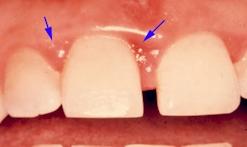

La récidive de la perte d'une restauration d'angle incisif doit éveiller l'attention du praticien sur la possibilité de problèmes occlusodontiques.

La gingivite localisée peut avoir pour cause des malrelations dento-dentaires.

Une simple fissure gingivale doit mettre le praticien en éveil.